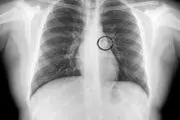

• در این تصویر علائمی که نشان می‌دهد باید سی‌تی اسکن ریه انجام شود را ببینید.

• پدر و مادر نگران با عجله دختر 9 ساله شان را به بیمارستان بردند تا متوجه واقعیت ماجرا شوند ؛ نتیجه ی عکسبرداری اورژانسی آنها را حیرت زده ساخت.